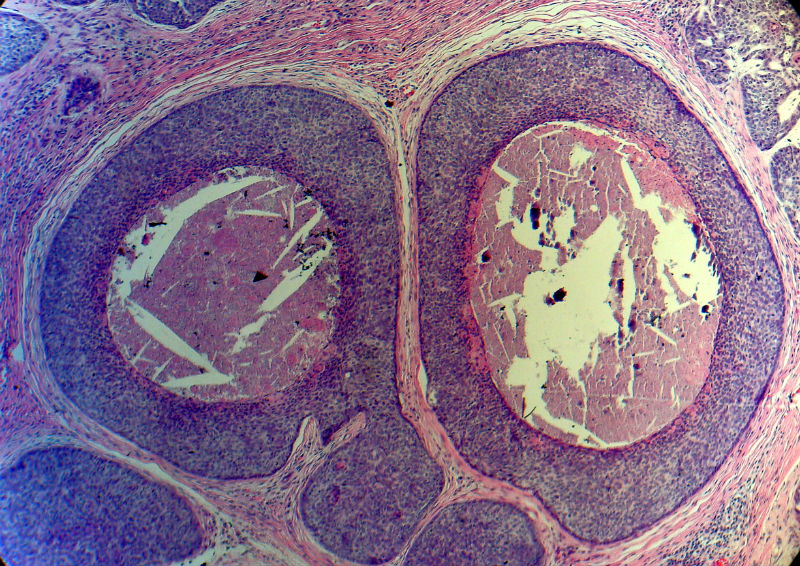

男,49岁,后枕部肿物3年,偶有破溃出血。

大体:皮肤半球形隆起,大小约2.3×2厘米,高出皮表0.8厘米,切面灰白,质地细腻。

基地细胞癌。粉刺样坏死型。

基底细胞癌。

似乎既有腺样结构,也有角化珠形成,还有细胞团内的粉刺样坏死。

有坏死、囊肿、钙化及胆固醇样裂隙等结构

考虑外毛根鞘肿瘤,局部癌变。